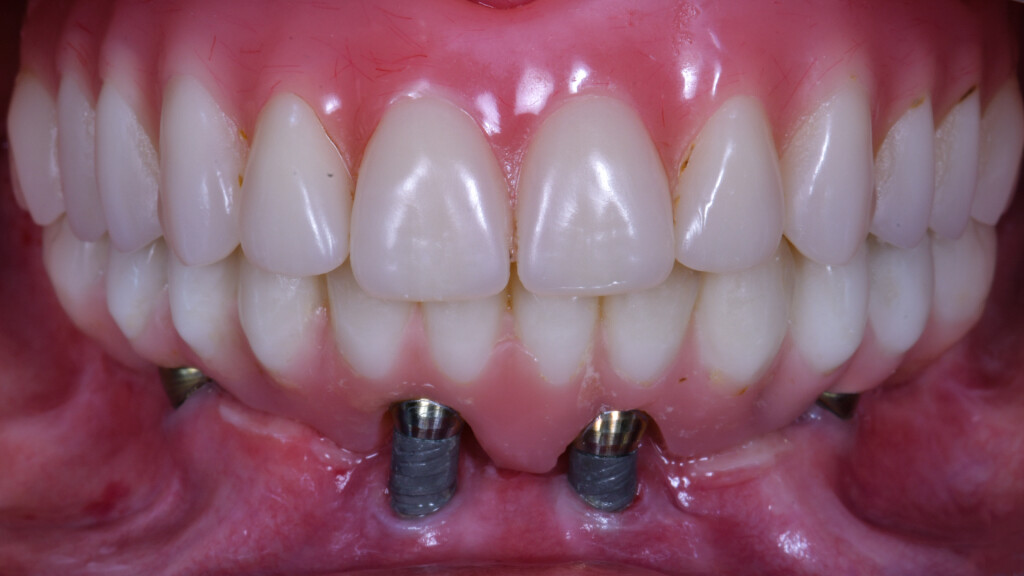

Come si può osservare dal video, gli impianti non sono in perimplantite: semplicemente, l’osso si è riassorbito attorno lasciandoli fuori.

Per fortuna anche gli impianti penso fossero low cost, perché non ho avuto grandi difficoltà a svitarli, pur dopo quattro anni.